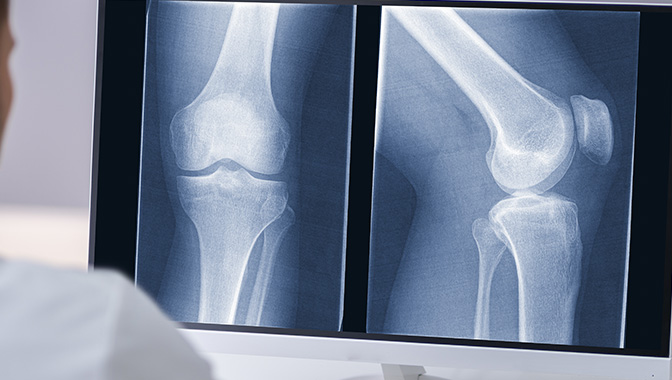

X-ray 검사

X선을 이용하여 조영제나 기구 등을 사용하지 않고 인체를 촬영하는 것으로,

전후 사진 또는 필요에 따라 측면 또는 대각선 촬영 등을 하게 됩니다.

흉부, 복부, 골격, 부비동, 경부연조직, 유방 등을 촬영하여 검사합니다.

• 보통 가슴사진, 허리 사진, 팔/다리 사진 등을 사전 준비 없이 검사하실 수 있습니다.

하지만, 촬영에 방해가 되거나 잘못된 판독을 할 수 있는 장신구들을 빼고 촬영해야 합니다. 특히 여성의 경우 금속성 악세사리가 달려있는 속옷은 탈의하시고 준비된 가운으로 바꿔 입으셔야 합니다.